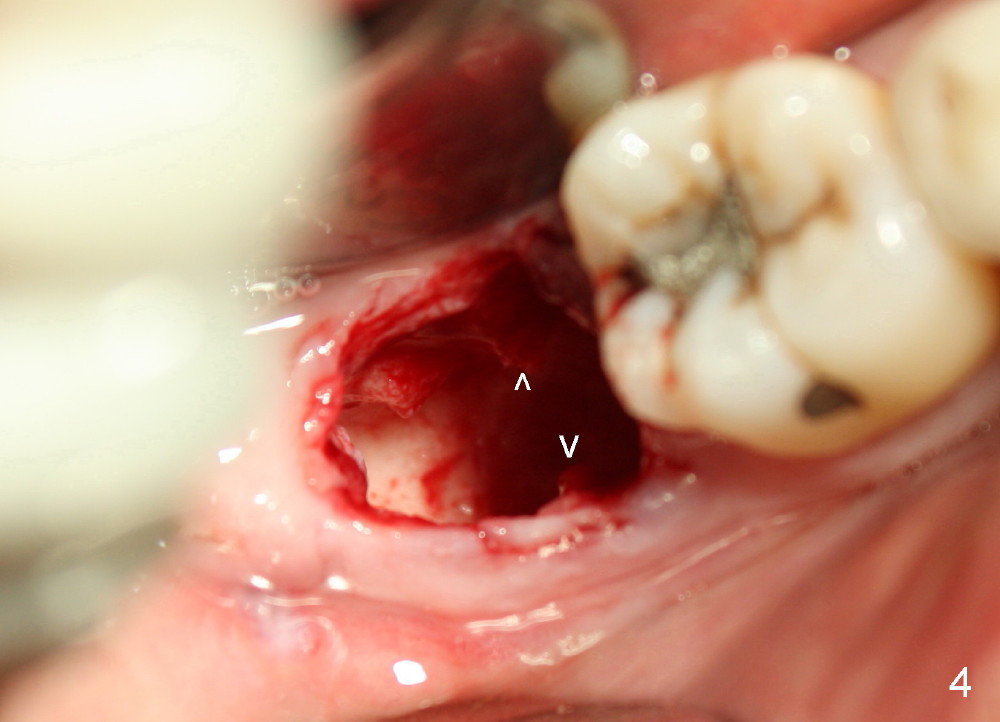

The tooth #31 of a 38-year-old lady has endo perio disease (Fig.1). Due to the large periapical lesion, there will be no solid (new) bone available for primary stability of an immediate implant (Fig.2: 7x17 mm). Yellow dashed line represents the upper border of the Inferior Alveolar Canal (IAC). Infiltration anesthesia is administered first. The mesiodistal widths of the root of the extracted tooth are 10 and 7 mm at the coronal and apical ends, respectively; the buccolingual ones 7 and 5 mm; the length 17 mm (Fig.3). The socket appears much larger than the root (Fig.4). To prevent paresthesia, no drills are used. Instead, a series of tap drills (6,7,8x17 mm) are sequentially inserted into the socket. The largest tap (Fig.5 T; 8x17 mm) binds to the socket securely with separation from IAC. Block anesthesia has to be administered before removal of the tap. A tapered implant (8x17 mm) is placed with insertion torque greater than 60 Ncm (Fig.6 I); allograft mixed with Osteogen is placed around the implant (*). Collagen dressing covers the opening of the remaining socket. The wound is protected with perio dressing, which is partially secured by an abutment (A in Fig.6). No paresthesia is reported by the patient a few hours postop.